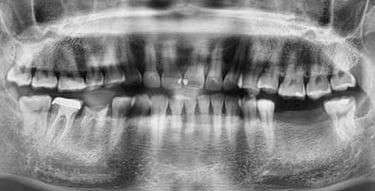

Reabilitare implantara in cazul unor dinti restanti irecuperabili, cu mobilitate severa. Dupa extractia atraumatica a dintilor compromisi, tratamentul continua cu inserarea implanturilor dentare. In prealabil, in urma cu 6 luni s-a realizat aditie osoasa prin sinus lift extern la nivelul cadranului II, tehnica chirurgicala care ne-a permis inserarea implanturile posterioare.